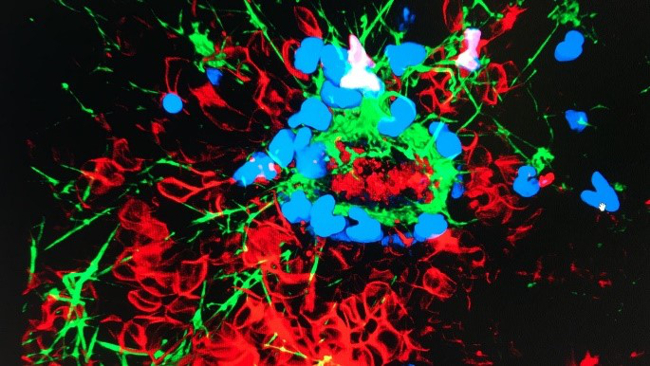

Simon Mathis, Gabriel Putzer, Martin Hermann, Lisa Schnegg, Judith Martini

A central objective of our group is to shed light on the endothelial glycocalyx and microcirculation during liver transplantation. It is already known that, during harvesting, storage on ice and subsequent reperfusion of the graft in the recipient, ischaemia reperfusion injury occurs with destruction of the glycocalyx, which is associated with poorer graft function and recipient outcome. With a new form of storage (normothermic machine perfusion), there is hope that the glycocalyx and therefore microperfusion of the graft will be better preserved. The working group is currently conducting two studies on this topic: a clinical study is investigating the effect of normothermic machine perfusion on the glycocalyx and the effects of endothelial glycocalyx shedding on perioperative organ function; an animal study is attempting to attenuate destruction of the glycocalyx through pharmacological adaptation of the perfusion solution during normothermic machine perfusion.

- Putzer, G.; Martini, J.; Gasteiger, L.; Mathis, S.; Breitkopf, R.; Hell, T.; van Enckevort, A.; Oberhuber, R.; Öfner, D.; Schneeberger, S.: Liver Transplantation Activity in the Eurotransplant Area Is Recovering Slowly During the COVID-19 Crisis. TRANSPLANTATION DIRECT. 2020; 6(11): e611.

- Cardini, B.; Oberhuber, R.; Fodor, M.; Hautz, T.; Margreiter, C.; Resch, T.; Scheidl, S.; Maglione, M.; Bösmüller, C.; Mair, H.; Frank, M.; Augustin, F.; Griesmacher, A.; Schennach, H.; Martini, J.; Breitkopf, R.; Eschertzhuber, S.; Pajk, W.; Obwegeser, A.; Tilg, H.; Watson, C.; Öfner, D.; Weissenbacher, A.; Schneeberger, S.: Clinical Implementation of Prolonged Liver Preservation and Monitoring Through Normothermic Machine Perfusion in Liver Transplantation. TRANSPLANTATION. 2020; 104(9): 1917-1928.

- Confocal microscope laboratory